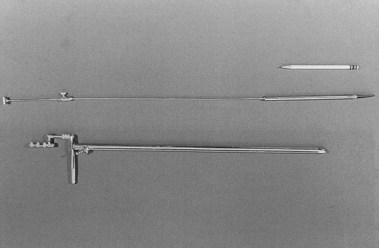

随着可视化仪器的出现,很明显必须获取组织来确定所观察到的异常的性质。早期使用盲活检仪器,但需要一种装置,使操作员能够在内窥镜检查时直接获取异常组织的活检标本。Benedict 手术胃镜于 1948 年基于 Kenamore 1940 年的型号制造而成(图 1.7)。Benedict仪器(我在 1960 年接受过培训)是一种广泛使用的流行仪器。在关于活检必要性的争论中,Benedict(最初是一名完全转向内窥镜检查的外科医生)表示,胃镜检查不是常规程序,应该保留用于鉴别诊断中的难题,但“除非胃镜医师有一些现成的活检方法,否则胃镜检查是不完整的。” 很快人们就发现,组织学检查与仅基于可视化的诊断之间的相关性往往存在很大差异,某些诊断若不进行组织检查则无法可靠地做出。诸如冲洗和刷检细胞学等方法的探索仍在继续,并以各种形式延续至今。

图 1.7Benedict 手术胃镜。